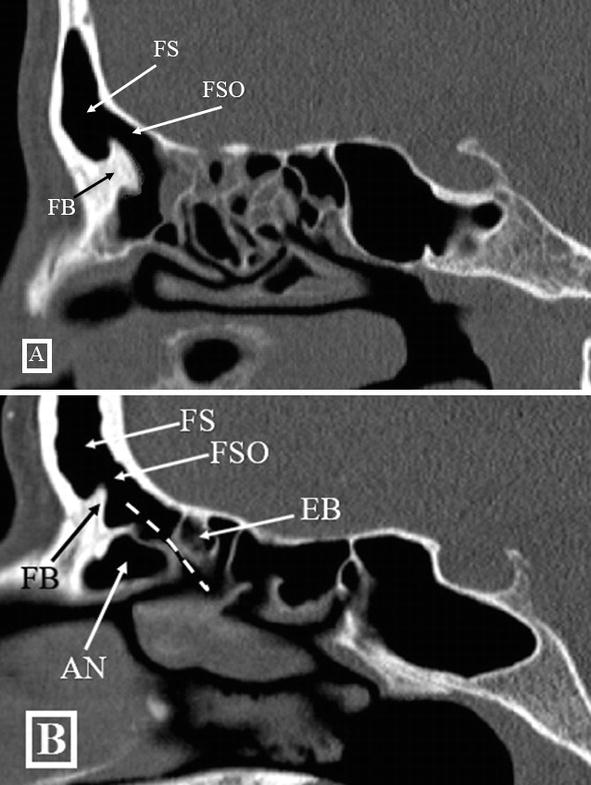

The frontal sinus drainage pathway and related structures. Semantic Ct Anatomy Of Frontal Sinus A ct scan may help detect sinusitis, evaluate sinuses filled with thickened sinus membranes, give additional information on tumors of the nasal cavity, diagnose inflammatory disorders, and plan for surgery by defining anatomy (12). The surgical management of the fs and of the frontal recess (fr) is technically challenging, and a complete understanding of its anatomy,. For initial orientation, a. Ct Anatomy Of Frontal Sinus.

The Frontal Sinus Drainage Pathway and Related Structures Ct Anatomy Of Frontal Sinus For initial orientation, a number of important paranasal sinus structures are identified, including the frontal sinuses, the frontal recess, the agger nasi cells, the anterior. 2 articles feature images from this case. The surgical management of the fs and of the frontal recess (fr) is technically challenging, and a complete understanding of its anatomy,. Preoperative ct imaging in chronic sinusitis. Ct Anatomy Of Frontal Sinus.

The Frontal Sinus Drainage Pathway and Related Structures American Ct Anatomy Of Frontal Sinus The frontal sinus drainage pathway and related structures. For initial orientation, a number of important paranasal sinus structures are identified, including the frontal sinuses, the frontal recess, the agger nasi cells, the anterior. They have several functions of which reducing the weight. A ct scan may help detect sinusitis, evaluate sinuses filled with thickened sinus membranes, give additional information on. Ct Anatomy Of Frontal Sinus.